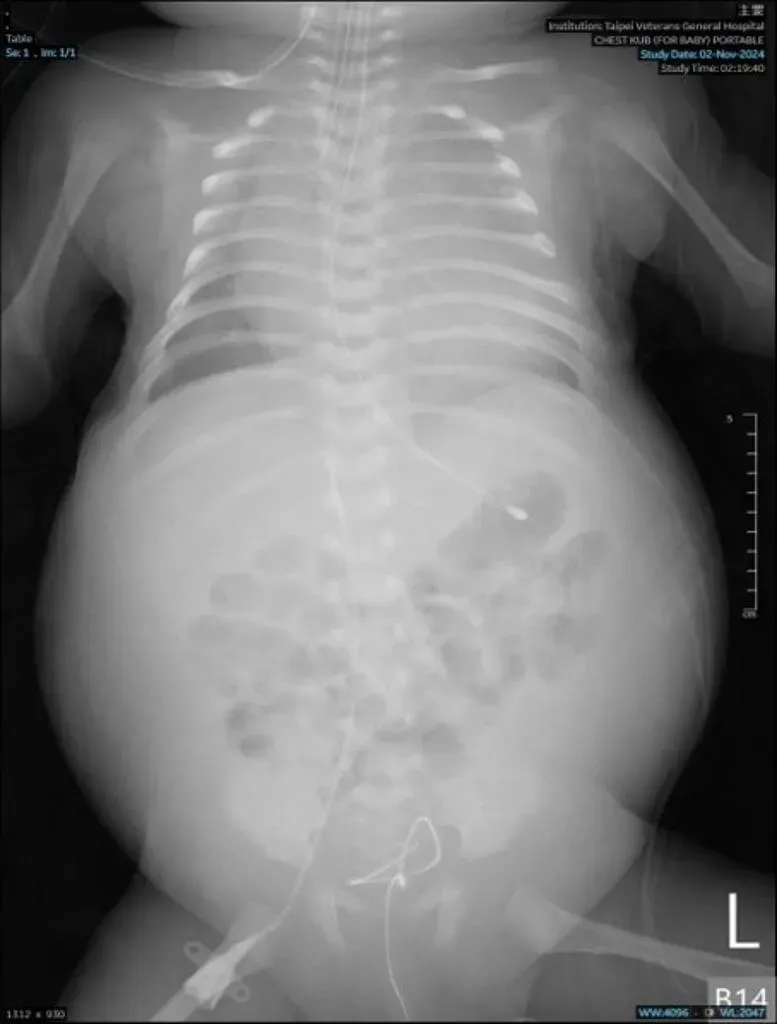

嬰兒

小兒科醫師傑登

北榮

呼吸困難

罕見疾病